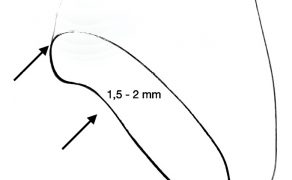

- Mechanika powstawania pionowych pęknięć i złamań zębów.

Zespół pękniętego zęba (cracked tooth syndrome, CTS) został opisany i zdefiniowany po raz pierwszy w 1976 roku przez Camerona (1). Opisany jest jako niecałkowite pęknięcie zęba z żywą miazgą obejmujące swoim zasięgiem zębinę i prawdopodobnie miazgę zęba. Objawy sugerujące wystąpienie syndromu pękniętego zęba to ból na nagryzanie podczas spożywania zimnych i gorących pokarmów. Nacisk okluzyjny podczas żucia powoduje ruch odłamów względem siebie, co z kolei powoduje rozprzestrzenianie się pęknięcia aż do miazgi zęba, wywołując stan zapalny spowodowany mikroprzeciekiem bakteryjnym. Rozprzestrzenianie się zapalenia prowadzi do nieodwracalnego zapalenia miazgi wymagającego leczenia endodontycznego. Wśród przyczyn powodujących występowanie pęknięć w obrębie [...]